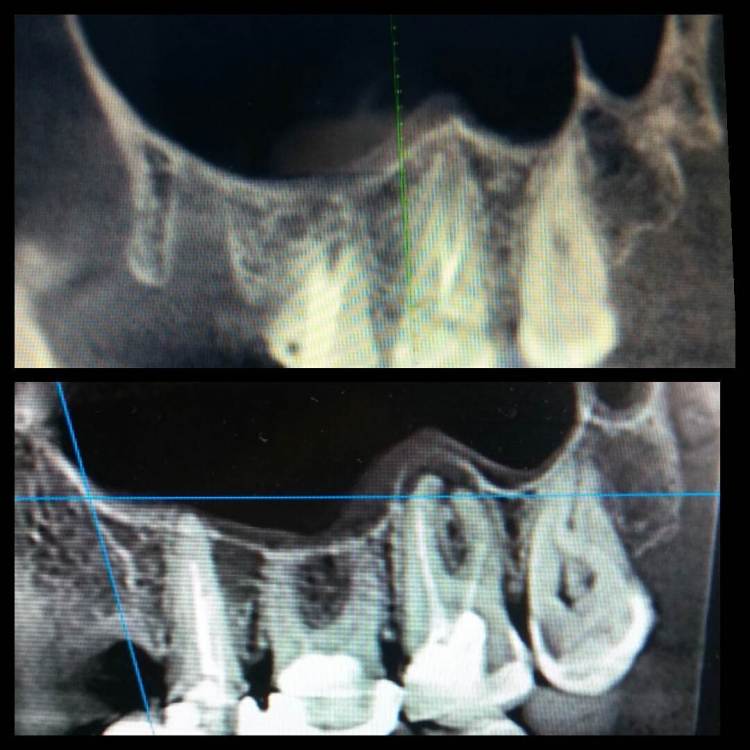

Еленаж Опубликовано 17 октября, 2022 Поделиться Опубликовано 17 октября, 2022 (изменено) Здравствуйте всем! Подскажите, пожалуйста, почему не затягивается лунка уже четвертый месяц? 15 июля удалила 25 зуб с периодонтитом, заживало всё нормально, была на осмотре у доктора и он сказал, что неделю, две и лунка закроется. Но она так и не затянулась. Самое печальное в сложившейся ситуации, что я не могу поставить акриловый протез и , боюсь, что зубы начнут двигаться. Да и жевать на этой стороне не имею возможности. Подскажите, почему так может быть? Возраст 39 лет, женщина. На снимке до удаления и спустя три месяца. Изменено 17 октября, 2022 пользователем Еленаж Ссылка на комментарий

Еленаж Опубликовано 17 октября, 2022 Автор Поделиться Опубликовано 17 октября, 2022 Фото не передаёт , как выглядит на самом деле лунка. В один день я и мама удалили зубы, я 25-й, она такой же 15-й , у нее к вечеру был фибрин, а через неделю просто пятнышко на ровном месте. А у меня между боковыми стенками пространство, которое никак не могу уловить на фото. Ссылка на комментарий